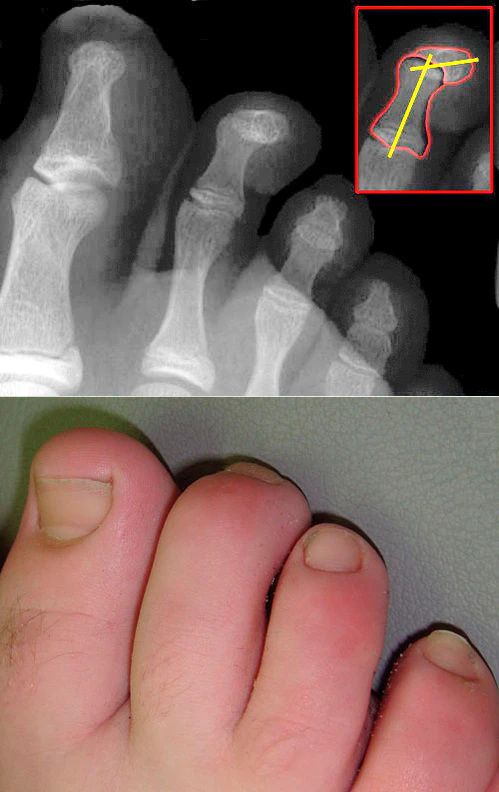

Молоткообразная деформация пальцев стопы

Молоткообразная деформация пальцев стопы (молоткообразные пальцы) — это наиболее распространённая деформация второго, третьего и четвертого пальцев стопы.

Проявляется из-за сгибательной контрактуры проксимального межфалангового сустава, переразгибания плюснефалангового и дистального межфалангового суставов. В результате чего пальцы приобретают форму молоточка. Молоткообразная деформация пальцев стопы — это следствие сложной общей деформации стопы. Данная деформация возникает вследствие нарушения натяжения сухожилий мышц-сгибателей, а также из-за снижения подвижности межфаланговых суставов пальцев стопы. При снижении активности пальцев суставы как бы фиксируются в согнутом состоянии.[1]

Очень часто молоткообразная деформация пальцев сопровождается такими ортопедическими патологиями как: вальгусная деформация большого пальца, поперечное плоскостопие, церебральный паралич, полиомиелит, миелодиспластическая полая стопа и др. Данная деформация стопы опасна таким осложнением, как развитие отстеоартроза вследствие подвывиха фаланг пальцев. Также при этом недуге образуются большие мозоли и натоптыши из-за сильного давления и постоянного трения обуви.